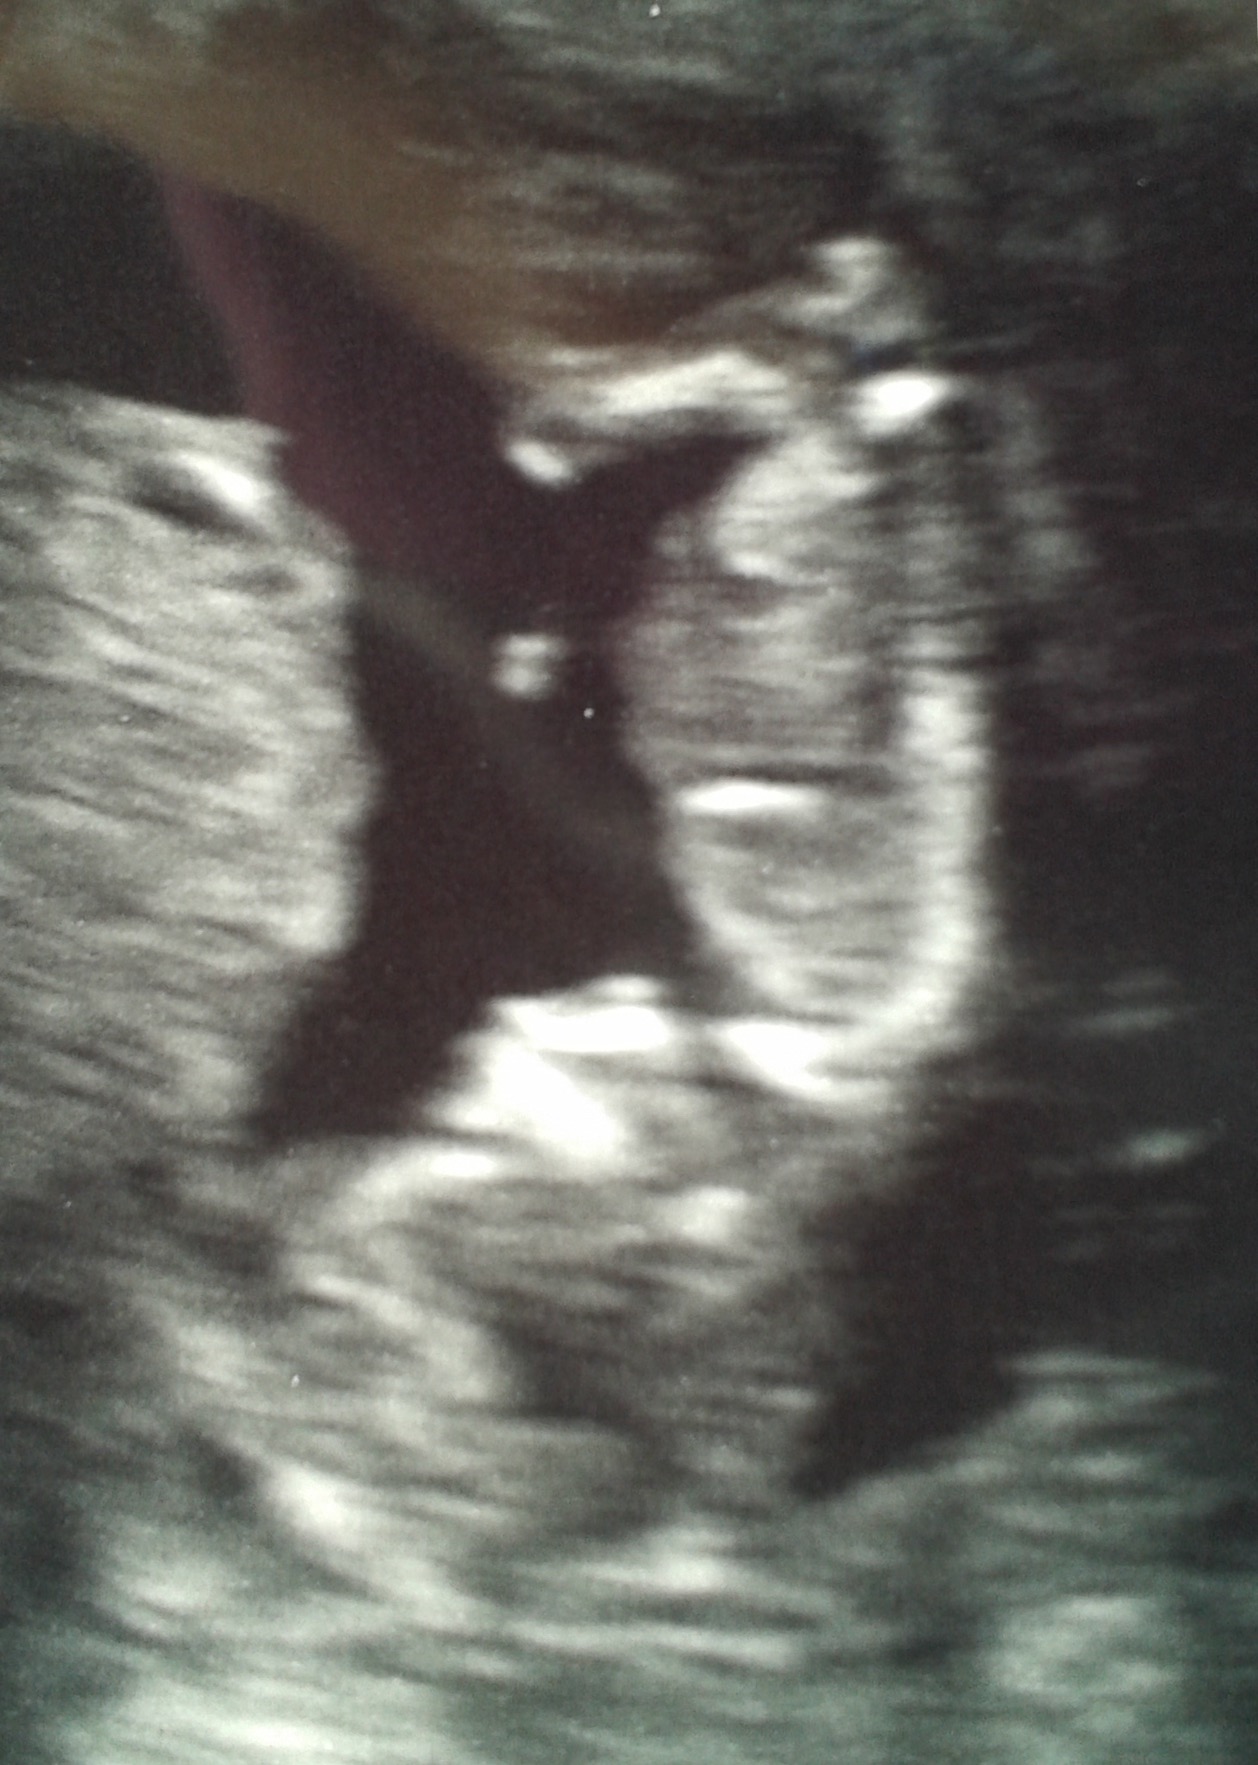

15w2d -- little boy is camera shy! He's laying with his arm curled under his face. His face resembles a Halloween mask! Lol super active with a heartbeat going from 144-151. Stretched out with his feet on one side, and head on the other.